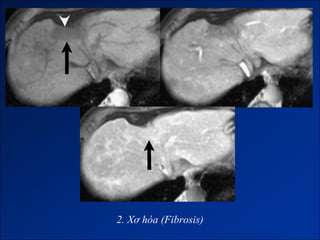

2. Xơ hóa trong gan xơ (Fibriosis).

2. Xơ hóa (Fibrosis)